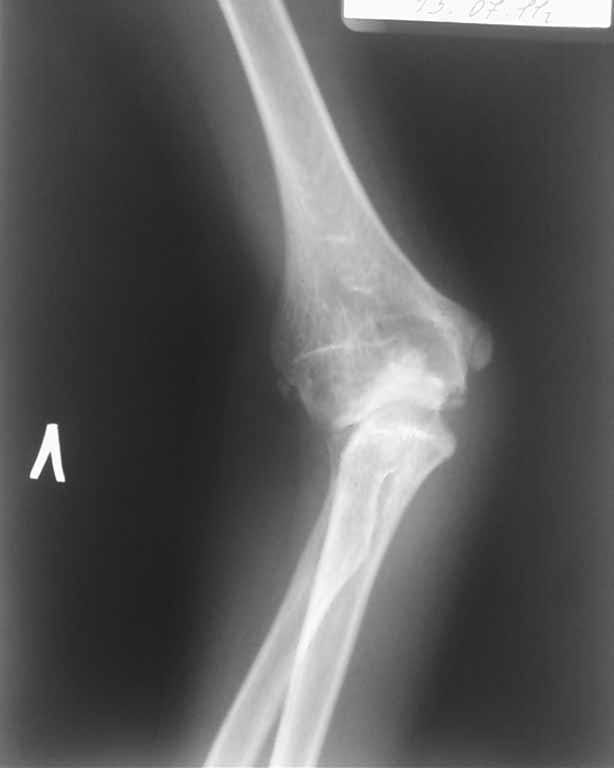

Ответ собственно на все вопросы на боковой рентгенограмме: вывих лучевой кости. Либо перенесенный недиагносцированный-нелеченный Монтедж (повреждение Монтаджа: вывих лучевой кости с переломом локтевой кости). Более редкий вариант (скорее всего выявили бы раньше - врожденный вывих лучевой кости. Но честно говоря патология крайне редкая, да и не очень похоже.

Присмотрелся к боковой рентгенограмме сейчас... А можно повторить снимки в более стандартных укладках? А то складывается ощущение полного вывиха костей предплечья... Или это шутка укладки... Все-таки 7 лет жить с вывихом в локтевом суставе как-то нонсенс... Или все совсем запущено и предыдущий пост отменяется.

Клинически: отмечается вальгусная деформация локтевого сустава 32º, передневнутренний вывих головки лучевой кости. Разгибание 175º, сгибание 82º.

На рентгенограмме. Нарушение пропорциональности дистальных структур плечевой кости не отмечается. Объемная деформация головки лучевой кости не визуализируется, отмечается передневнутренний вывих головки лучевой кости. Отмечается нарушение сферичности локтевой вырезки, объемный дефицит суставной поверхности, который привел к объемному конфликту в плечелоктевом суставе, став причиной ограничения сгибания. Гипертрофия венечного отростка, увеличение ширины локтевого отростка в боковой проекции. Все эти изменения свидетельствуют о перенесенном переломе в области локтевого отростка.

Исходя из деформации в локтевом суставе, причиной которого не является деформация дистального конца правой плечевой кости (линия Маркса не нарушена (иллюстрирована красными линиями на рентгенограмме)). Мы подозревали неправильно сросшийся перелом проксимального отдела локтевой кости, при котором со временем произошло самоисправление. С целью устранение вальгусной деформации и для восстановления сферичности локтевой вырезки, устранения объемного конфликта в плечелоктевом суставе произвели двухплоскостную корригирующую остеотомию у основания венечного отростка локтевой кости и остеосинтез спицами.